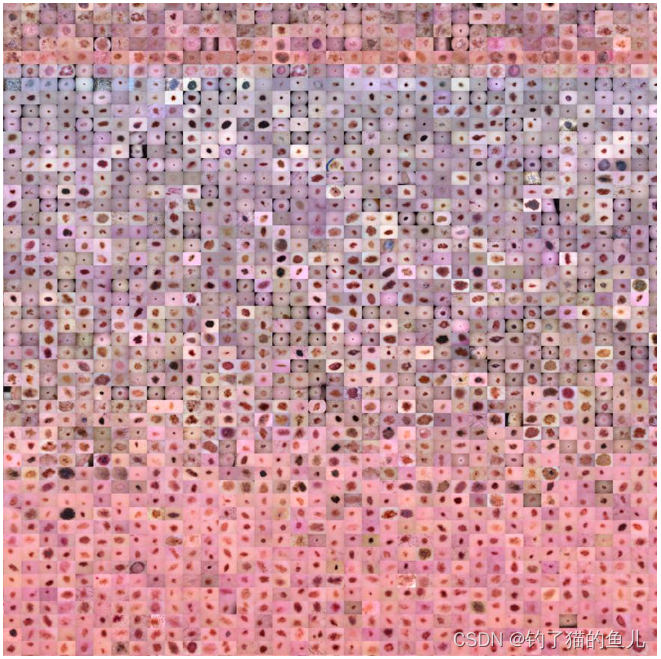

HAM10000是一个包含10000张训练图像的数据集,用于检测色素性皮肤病变。该数据集的作者从不同人群中收集了皮肤镜图像,这些图像由不同的方式获取和存储。

论文摘要:由于可用于皮肤镜图像的数据集规模较小且缺乏多样性,神经网络的训练在色素性皮肤病变的自动诊断方面受到了阻碍。我们通过发布HAM10000(“人类与机器对决,拥有10000张训练图像”)数据集来解决这个问题。我们收集了来自不同人群的皮肤镜图像,这些图像通过不同的方式获取和存储。鉴于这种多样性,我们不得不应用不同的获取和清洁方法,并开发了利用专门训练的神经网络的半自动工作流程。最终的数据集包含10015张皮肤镜图像,作为学术机器学习目的的训练集发布,并通过ISIC档案公开可用。这个基准数据集可用于机器学习和与人类专家进行比较。案例包括色素性病变领域中所有重要诊断类别的代表性集合。超过50%的病变已经通过病理学确认,而其余病例的真实情况则通过随访、专家共识或体内共聚焦显微镜确认。